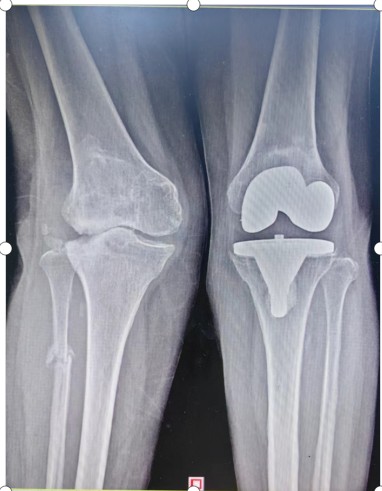

入院后羅湘平主任醫(yī)師、彭健副主任醫(yī)生及蔣瀟純主治醫(yī)師查體時(shí)發(fā)現(xiàn)劉奶奶的右膝關(guān)節(jié)重度外翻,內(nèi)側(cè)副韌帶松弛嚴(yán)重致膝關(guān)節(jié)失去穩(wěn)定性。CT檢查發(fā)現(xiàn)右膝關(guān)節(jié)外側(cè)脛骨平臺(tái)缺損明顯,深度達(dá)1.5厘米以上,長(zhǎng)期應(yīng)力異常,導(dǎo)致腓骨近端應(yīng)力性骨折。這種復(fù)雜膝關(guān)節(jié)畸形行人工膝關(guān)節(jié)置換不但技術(shù)難度大,而且費(fèi)用很高。根據(jù)劉奶奶膝關(guān)節(jié)評(píng)估結(jié)果,可能需要行鉸鏈膝關(guān)節(jié)假體及金屬墊塊充填骨缺損,僅假體材料費(fèi)用就要達(dá)6萬(wàn)余元,普通家庭無(wú)法承受。

羅湘平主任醫(yī)師團(tuán)隊(duì)考慮患者的家庭經(jīng)濟(jì)狀況,決定力爭(zhēng)修復(fù)患者原有的解剖結(jié)構(gòu),避免使用更多的人工替代品,以減少患者的經(jīng)濟(jì)負(fù)擔(dān)。為了能夠順利完成手術(shù)、達(dá)到滿(mǎn)意的效果,羅湘平主任醫(yī)師做好充分的術(shù)前準(zhǔn)備工作,精心設(shè)計(jì)手術(shù)方案,選擇為患者實(shí)施普通的人工膝關(guān)節(jié)置換,內(nèi)側(cè)副韌帶止點(diǎn)采用螺絲重建術(shù)恢復(fù)膝關(guān)節(jié)穩(wěn)定性,脛骨外側(cè)平臺(tái)骨缺損采用螺絲釘加骨髓泥充填,為患者節(jié)省3萬(wàn)余元材料費(fèi)。劉奶奶的膝關(guān)節(jié)畸形得到矯正、恢復(fù)了穩(wěn)定性,于術(shù)后第10天順利出院。

術(shù)前

術(shù)后